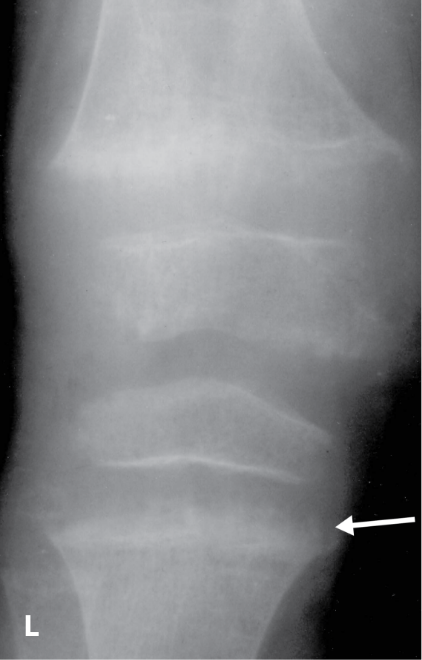

The RSS is a quantitative method that uses radiographs to assess the severity of rickets at the wrists and knees. Originally validated in nutritional rickets, the score is based on the degree of metaphyseal fraying, metaphyseal cupping, and the proportion of the growth plate that is affected. It is a 10-point scale, for which 10 represents the most severe radiographic changes due to rickets and 0 represents the absence of these changes.1

Although the severity and duration of rickets vary considerably between XLH and nutritional rickets, the radiographic features of rickets at the growth plate are similar in the two disorders, which allowed validation of the RSS in XLH. The RSS correlates with serum alkaline phosphatase (ALP) levels, a biochemical marker of rachitic activity, and this scoring system can be used to assess the radiographic response following treatment of nutritional or XLH rickets.

The RSS in XLH has been reported to range from 0 to 4.5; however, despite the smaller RSS range observed in XLH patients, inter- and intra-rater reliability are similar to those reported for nutritional rickets. Patients with XLH who had a baseline RSS ≥1.5 were shown to have more severe hypophosphatemic bone disease, including higher levels of alkaline phosphatase, and greater impairments in clinical outcomes compared with patients who had a baseline RSS <1.5.